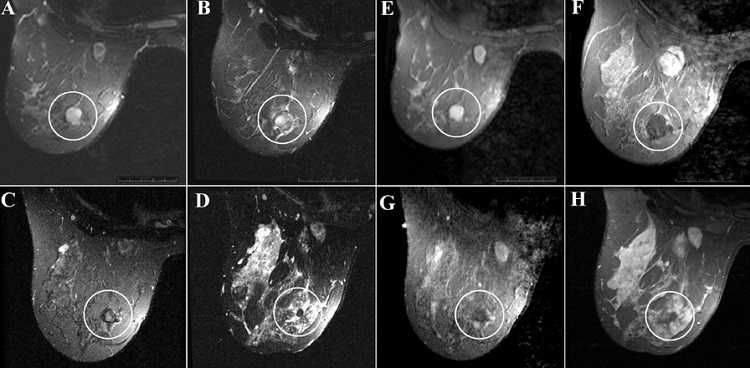

Фиброаденомой называют доброкачественное образование в молочной железе. Оно имеет четкие контуры, плотную внутреннюю консистенцию, легко перемещается в тканях груди. При этом нет боли в месте формирования опухоли.

Патология часто наблюдается у девушек и женщин до 40 лет. Обычно новообразование имеет размеры от 1 до 3 см, но встречаются и более крупные образования. В большинстве случаев фиброаденома молочной железы поражает одну грудь, иногда – обе. Могут встречаться множественные новообразования.

Фиброаденома не угрожает жизни, но повышает риск развития рака в 5 раз. По этой причине нужно постоянно проходить обследования, следить за состоянием своего здоровья.